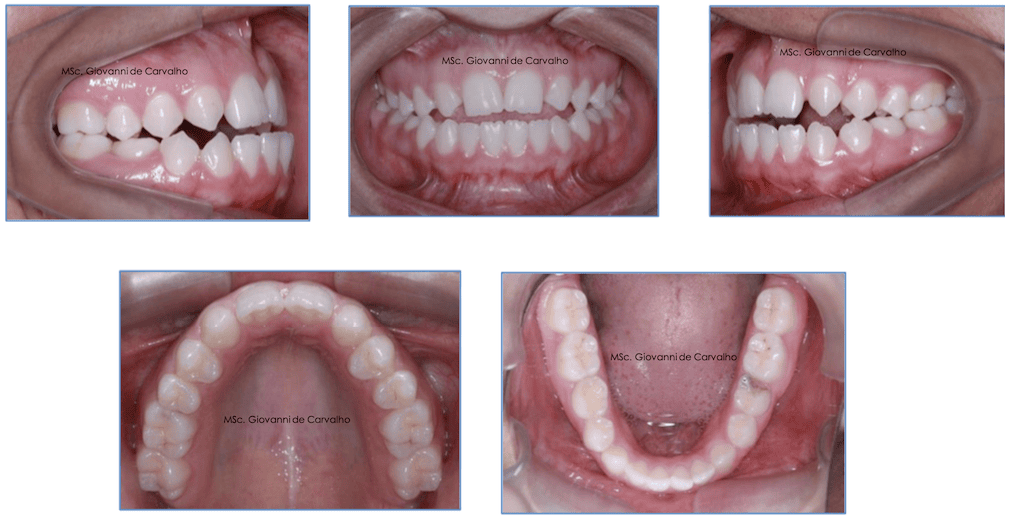

Todo sorriso tem uma história. Hoje quero compartilhar a trajetória da Thaís, uma jovem de 15 anos que chegou até nós bastante incomodada com sua mordida e com a forma como seus lábios se posicionavam. Sua queixa principal era: "Meus dentes não se tocam e meu lábio está muito para fora."

Esse tipo de alteração é conhecido em Ortodontia como Classe III de Angle, um nome técnico para um problema em que os dentes de baixo ficam mais para frente do que os de cima, causando a chamada "mordida cruzada" ou "mordida invertida". Esse tipo de desarmonia pode afetar o encaixe da mordida, o sorriso e até a estética facial.

No caso da Thaís, além dessa inversão da mordida, ela também apresentava ausência de alguns dentes permanentes (chamamos isso de agenesia) e mordida aberta, o que dificultava ainda mais a função mastigatória e a estética. Era um caso desafiador, mas que, com planejamento preciso e execução cuidadosa, trouxe um resultado transformador.

Durante a primeira avaliação, percebemos que Thaís tinha um perfil convexo, ou seja, o lábio inferior se projetava para frente, dando a sensação de que a boca estava sempre "forçando" o fechamento. Ela tinha todos os dentes permanentes, exceto os sisos, mas dois dentes importantes nunca se formaram: os incisivos laterais superiores. Além disso, mais tarde descobrimos também a ausência dos segundos pré-molares inferiores.

Sua mordida mostrava características típicas de Classe II, com dentes superiores inclinados para trás e uma mordida aberta de 2 mm, ou seja, os dentes da frente não se encontravam quando ela fechava a boca. Era um caso complexo, que exigia uma combinação de estratégias para devolver equilíbrio, estética e função.